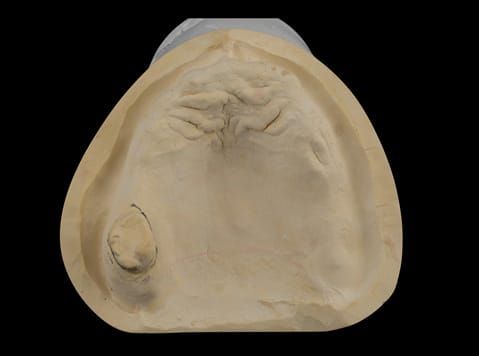

- Poorly fitting cobalt chromium based maxillary partial denture, which has been added to. This exhibited poor retention, stability and tissue fit (support). Unable to wear a new acrylic based denture.

- Cobalt chromium reinforced gasket denture - using a Molloplast B "O" ring to retain and stabilise the denture. This was my professional preference as this was the least invasive and simplest solution to this dental problem. Should the UR7 require removal in the future - an artificial tooth could be added - resulting in a complete denture. The patient would have adapted to the denture fully by this stage and have good neuromuscular control of the prosthesis.

Following consultation and second discussion appointment the patient chose to have option 2 namely, a window denture - maxillary cobalt chromium based partial denture. The clinical situation and treatment process is shown in detail below with photographs. The patient was successfully rehabilitated with this and her quality of life considerably improved. The clinical work was provided by Finlay and the technical work by Rowan.